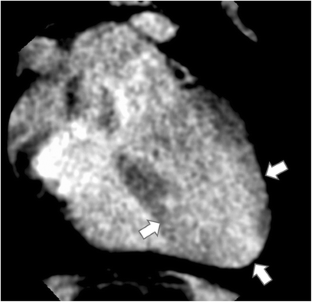

Fig. 3